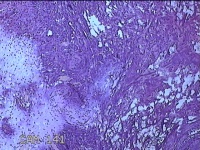

右输卵管异位病灶?

性别

女

年龄

26岁

临床诊断

右侧子宫内膜异位病灶

一般病史

停经52天。

标本名称

大体所见

灰白暗红色不规则碎组织2.3x2x0.3cm一堆。